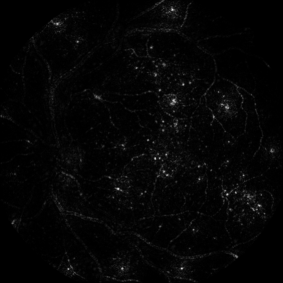

5.4 Visualization Artifacts

Artifacts from various visualization algorithms are illustrated in Fig. 4. First, it can be seen that the original sensitivity criterion is inadequate to finely detect lesions. Sensitivity maps seem to indicate that if lesions grew in size, the diagnosis would be consolidated. The hue constraint prevents the lesion detections from growing. Second, it can be seen that, due to the drafting effect, blood vessels (lesion confounders) in the vicinity of lesions are detected, both in the hue-constrained sensitivity maps and in the layer-wise relevance propagation maps. The resulting false detections are not necessarily connected to the true detection, so they cannot be removed easily through image post-processing techniques: they have to be removed beforehand, hence the proposed approach.

The performance of the proposed pixel-level detector, using ‘net B’, is illustrated in Fig. 9 and 10 on two images from independent datasets. The first image comes from the publicly-available Messidor dataset999http://www.adcis.net/en/Download-Third-Party/Messidor.html. The second image comes from a private dataset acquired with a low-cost handheld retinograph (Quellec et al., 2016a).

Three ConvNets were trained to detect referable DR in the Kaggle-train dataset, using the proposed heatmap optimization procedure. Then, we evaluated how well those ConvNets could detect lesions in the DiaretDB1 dataset, without retraining them. For lesion detection at the image level, they outperformed previous algorithms, which were explicitly trained to detect the target lesions, with pixel-level supervision (see Fig. 7). This superiority was observed for all lesions or groups of lesions, with the exception of ‘red lesions’. Experiments were also performed at the lesion level: for all lesion types, the proposed algorithm was found to outperform recent heatmap generation algorithms (see Table 3). As illustrated in two examples (see Fig. 9 and 10), the produced heatmaps are of very good quality. In particular, the false alarms detected on the vessels, in the vicinity of true lesions in the unoptimized heatmaps ( maps), are strongly reduced with sparsity maximization (, , ). These experiments validate the relevance of image-level supervision for lesion detectors, but stress the need to optimize the heatmaps, as proposed in this paper. Note that detection performance is not affected much by image quality: very good detections are produced in the blurry image obtained with a low-cost, handheld retinograph (see Fig. 10). This is a very important feature, which opens the way to automated mobile screening. However, it can be observed that the ‘AlexNet’ architecture, which achieves moderate DR detection results, also achieves poor detection results at the lesion level, even after heatmap optimization (see Table 3): to ensure good detection performance at the lesion level, the proposed optimization framework should be applied to ConvNet architectures that achieve good image-level performance.